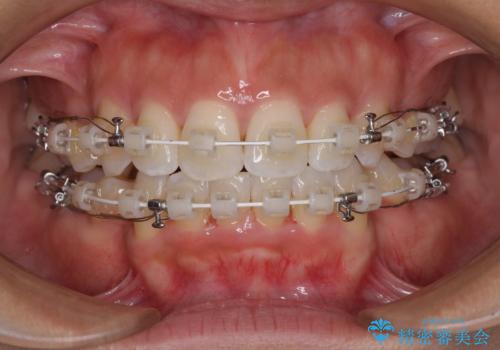

- 審美装置

- 2年3ヶ月

抜歯スペースに前歯を移動させることで歯の突出感が改善され、非常に唇が閉じやすい仕上がりとなりました。